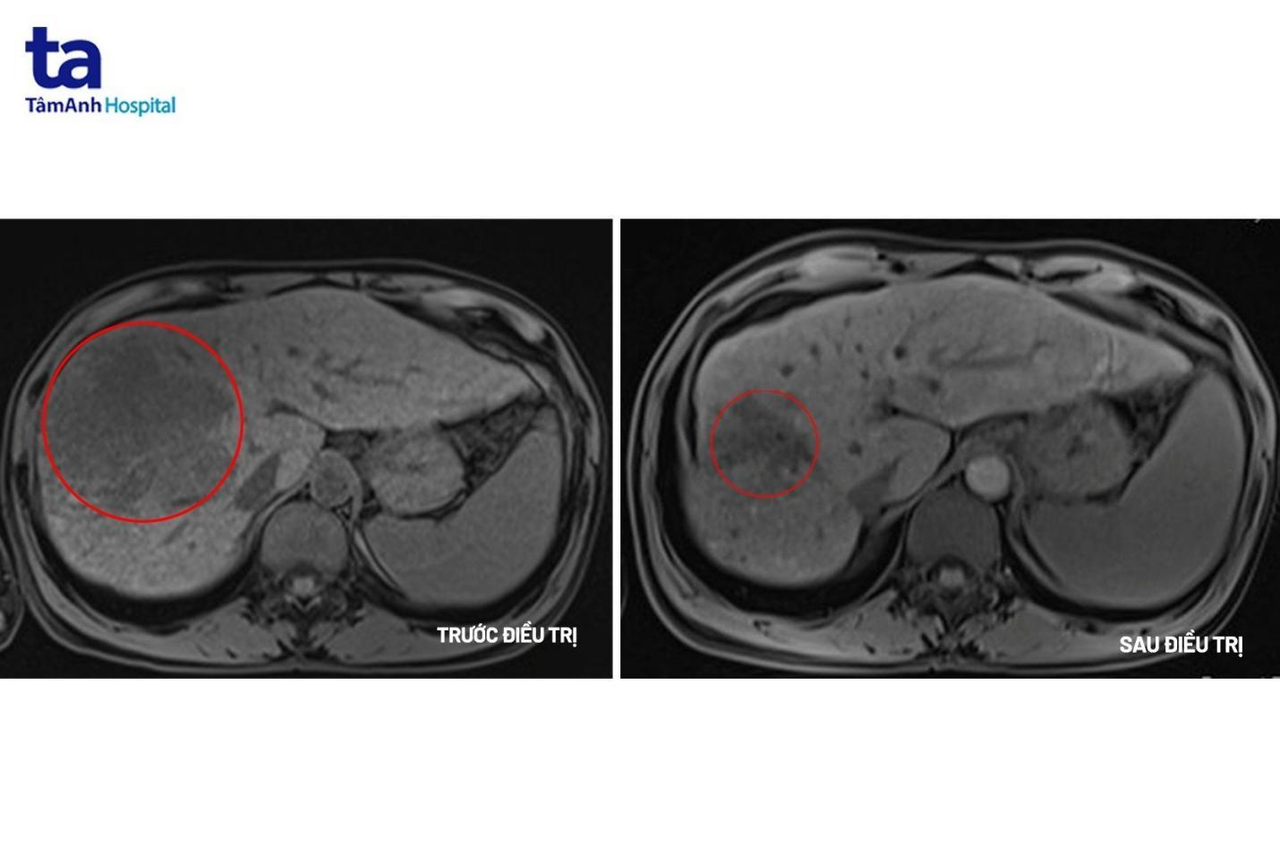

Xét nghiệm chỉ điểm ung thư gan cho thấy chỉ số AFP là 9412ng/mL (người bình thường chỉ số này là < 10ng/mL); AFP L3 81,3% (ngưỡng bình thường <10%); PIVKA II=56661 mAu/mL (ngưỡng bình thường <40 mAu/mL). Trên MRI cho thấy khối u lớn ở gan phải với kích thước 10x10x12cm có tính chất HCC, huyết khối tĩnh mạch cửa và xơ gan. Kết quả cho thấy người bệnh mắc ung thư gan giai đoạn muộn.

Sau 12 chu kỳ (khoảng 6 tháng) điều trị phác đồ miễn dịch kết hợp kháng thể đơn dòng, khối u gan đã giảm hơn 50% kích thước, người bệnh không xuất hiện triệu chứng đau, không có dịch ổ bụng, chức năng gan thận trở lại bình thường, cải thiện chất lượng cuộc sống. Bệnh nhân tiếp tục được điều trị và theo dõi chặt chẽ để nâng cao hiệu quả.

Hình ảnh khối u trước và sau điều trị. Ảnh: BVĐK Tâm Anh